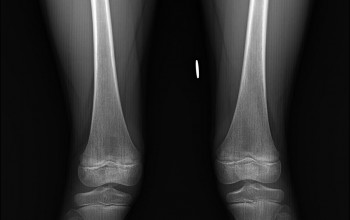

Wyposażyliśmy pracownię w cyfrowy detektor z oprogramowaniem posiadającym funkcję skalometrii (Stitching), dzieki której możliwe jest wykonanie badania telemetrycznego RTG całych kończyn długich i całego kręgosłupa a następnie uzyskanie obrazu diagnostycznego obejmującego razem kilka części anatomicznych połączonych w całość.

Skalometrie stosuje się w diagnostyce schorzeń ortopedycznych

Pomiary długości kości kończyn, kątowe pomiary skrzywień kręgosłupa